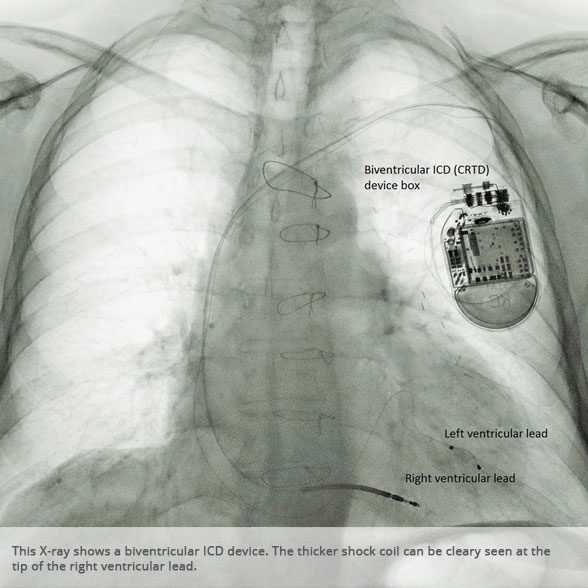

Biventricular ICD (CRTD) Biventricular ICD (CRTD)

Biventricular ICD (CRTD) device Biventricular ICD (CRTD) device

BI-VENTRICULAR PACEMAKERS

Bi-ventricular pacemakers are used for the treatment of suitable patients with heart failure who are already on medication but who suffer from a lack of synchrony between the right and left ventricular contraction. This is most commonly caused by an electrical delay (left bundle branch block LBBB) in transmission of signals to the main pumping chamber (called the left ventricle) and is relatively common in patients with advanced heart failure. This delay process commonly worsens the symptoms of heart failure and it is not generally influenced by medication alone.

Although not all patients universally respond to bi-ventricular pacing (or cardiac resynchronisation therapy/CRT), patients with more advanced dys-synchrony tend to experience remarkable improvement. Bi-ventricular ICDs have the additional benefit of recognising life threatening arrhythmia and deliver both fast pacing bursts or shocks to restore normal heart rhythm.